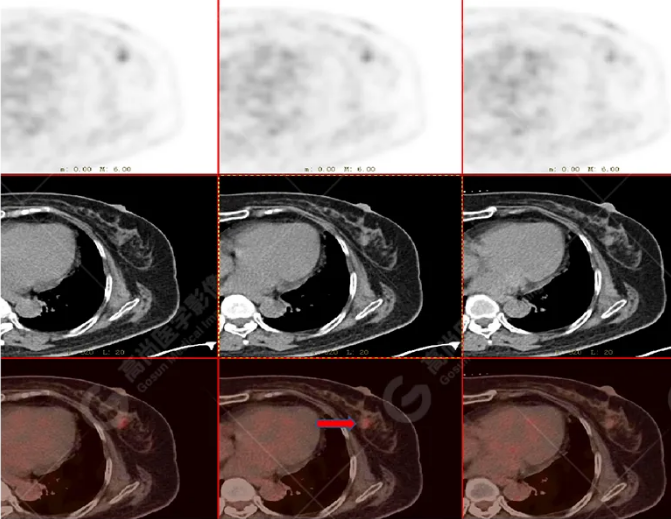

女性 67歲 因背痛查體,糖尿病11年。腫瘤標(biāo)記物:CEA 6.4↑,AFP、CA125、CA199正常。外院MR檢查:胸11椎體-附件左份異常信號(hào),增強(qiáng)環(huán)狀強(qiáng)化,骨原發(fā)?轉(zhuǎn)移?感染?PET/CT影像圖

胸椎溶骨性骨質(zhì)破壞,F(xiàn)DG環(huán)狀代謝增高,SUVmax為4.0。

左側(cè)乳腺一軟組織結(jié)節(jié),F(xiàn)DG代謝增高,SUVmax為2.6。

最終診斷:左側(cè)乳腺癌伴胸椎單發(fā)骨轉(zhuǎn)移。